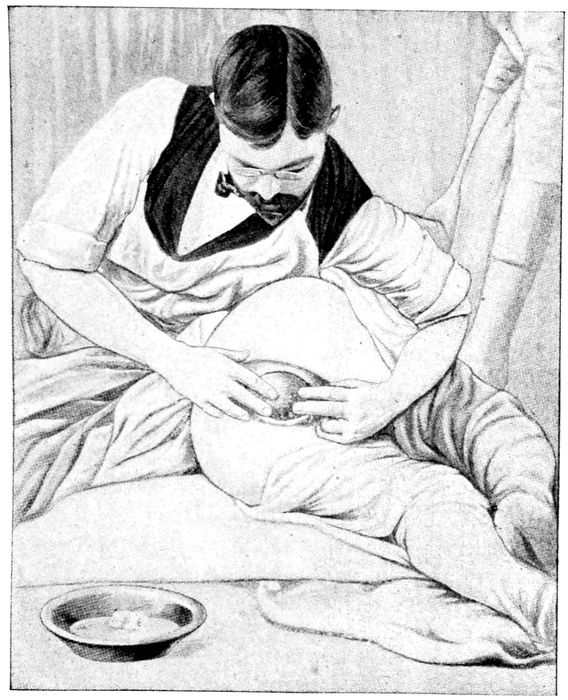

Palpation. What is in the pelvis? |

134 |

| |

| 54. |

Palpation. What is in the fundus? |

135 |

| |